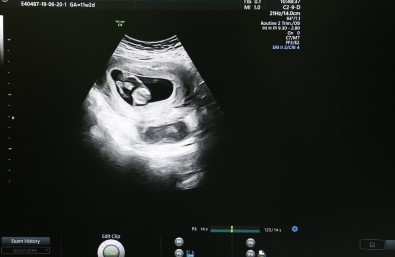

Sivas Cumhuriyet Üniversitesi Araştırma ve Uygulama Hastanesi, riskli gebeliklerin takibini “Ultrasonografi Cihazı” sayesinde kolaylıkla yapılabiliyor.

Yıldız, “Riskli gebelik takipleri kliniğimizde üst seviyede yapılabilmektedir. Özellikle bunun için gerekli altyapı konusunda hastanemiz bünyesinde üst düzey ultrasonografi cihazımız mevcuttur ve bu cihazı riskli gebelikler konusunda yaygın olarak kullanmaktayız ” dedi.

Cihaz sayesinde anne karnındaki bebeklerde zor ve güç olan problemleri kolaylıkla görüntüleyebildiklerini anlatan Doç. Dr. Çağlar Yıldız, “Bebeğin vücut yapısında bulunan tüm problemleri tespit edebiliyoruz. Örneğin; kalp, beyin gelişimiyle ilgili problemleri, kol ve bacak, yüz deformiteleriyle ilgili problemleri rahatlıkla ortaya koyabilmekteyiz” şeklinde konuştu.